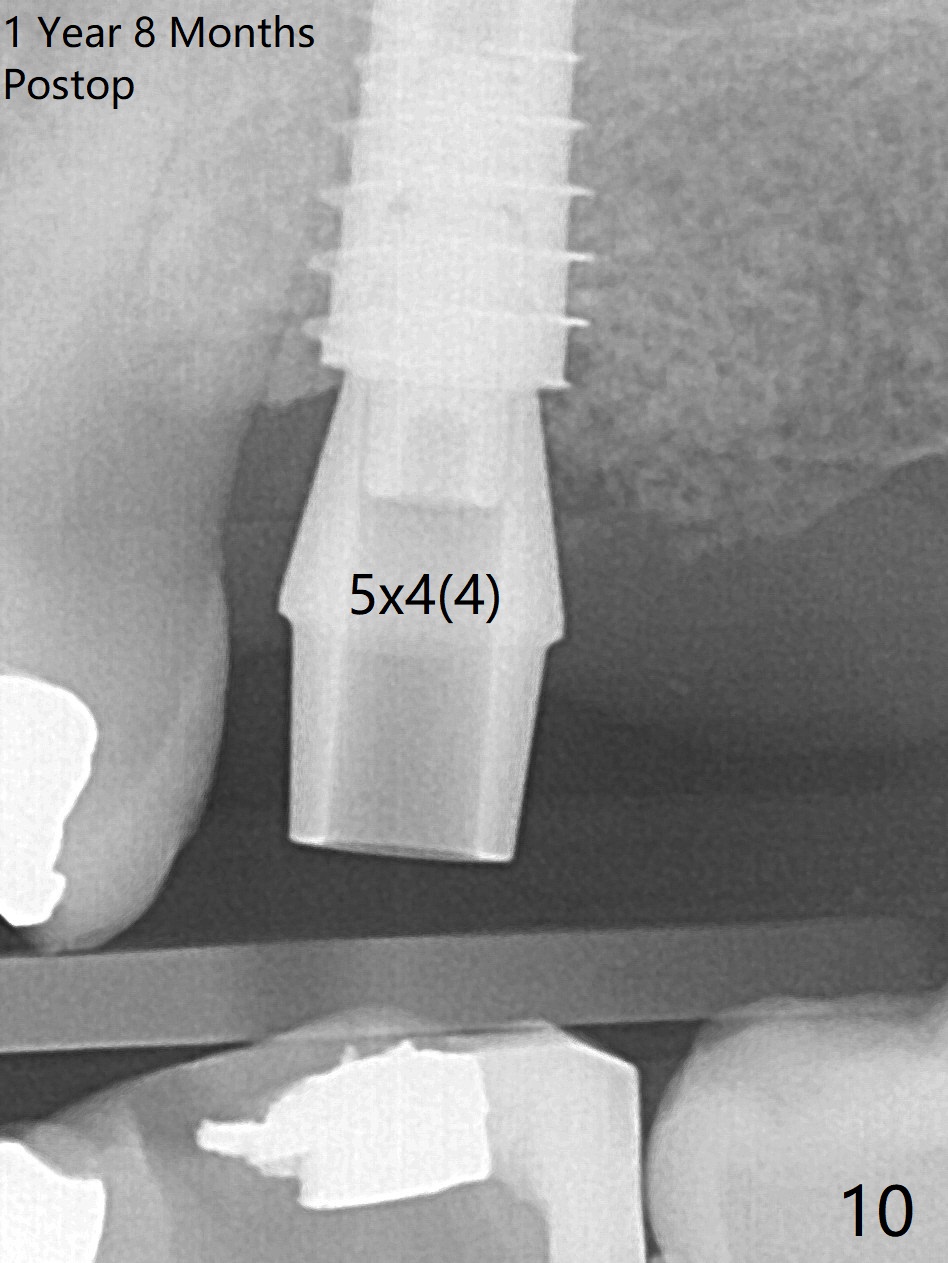

Designed osteotomy depth is 7.3 mm IS drill with 4 rings at #15. In fact osteotomy is created using 2.2 mm drill with 2 rings (sinus membrane barely visible from the osteotomy) and 3-4 mm ones with 3 rings. With an amalgam carrier of bone graft, sinus lift is initiated with 4x9 mm dummy implant (Fig.1). After loaded with totally 5 amalgam carriers of bone graft repeatedly with the 4x9 mm dummy implant, a 5x9 mm implant is placed with ~ 25 Ncm. After insertion of a 6x4(2) mm abutment, sticky bone cut into pieces (Fig.2) is inserted to peri implant space (Fig.3 *), followed by PRF and an immediate provisional. The latter dislodges 7 days postop; the socket starts to heal (Fig.4); the bone graft seems to be fixed in place. The provisional is reseated (no cement, Fig.5) without fear of its dislodgement again. The patient returns for cleaning 1 year 7 months postop (Fig.6,7). The socket heals, while the abutment is incompletely seated (Fig.7 <). Percussion at #18 disappears post RCT, whereas periapical radiolucency appears post RCT (compare Fig.8,9). When the 6x4(2) mm incompletely seated abutment is removed, the implant well is dirty. The smaller abutment with longer cuff is seated fully (Fig.10).